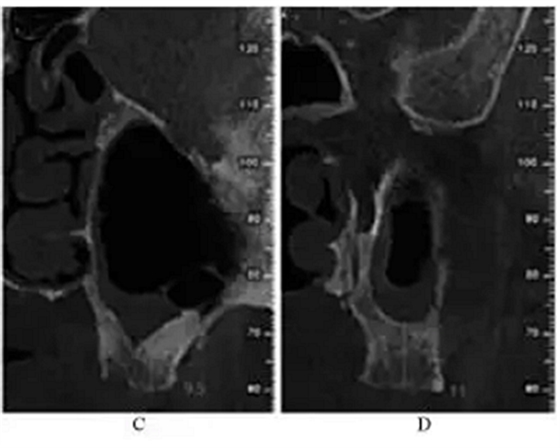

治疗过程:左侧上颌局麻下,于25~28牙区作梯形切口,翻瓣。用直径6mm的去骨环钻于25牙远中根尖处开窗,去除游离骨片,见窦膜完整,剥离窦膜。从开窗处穿刺抽出约2mL淡黄色粘稠液体,生理盐水加庆大霉素冲洗窦腔至冲洗液清亮,窦膜穿孔处放1.5 cm×2.5 cm胶原膜1片,在窦底与胶原膜之间植入骨粉1g,开窗表面覆盖2 cm×2.5 cm胶原膜1片及富血小板纤维蛋白膜3片,减张缝合(图2)。

图2 上颌窦外提升术中。注:A,开窗;B,抽出液体;C,植入骨粉;D,缝合。